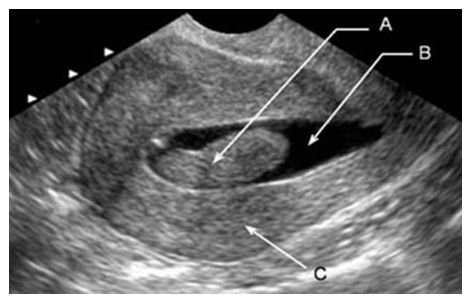

| Figure 5. Patient Kh-va, 49 years old. Source No. 878. Ultrasound image of a submucous node and grade I adenomyosis |